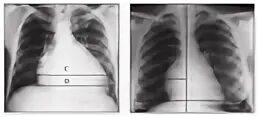

Что значит на рентгене расширена тень сердца